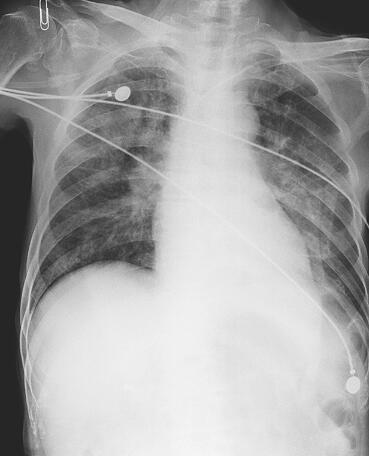

诊疗经过:患者入院后经验性应用拉氧头孢2g,每日2次抗感染,间断后鼻道吸痰,予吸氧、雾化、祛痰、平喘、补液等常规治疗。患者体温进行性下降,6月22日痰培养回报铜绿假单胞菌,对头孢菌素、喹喏酮类、碳氢霉烯类抗生素敏感。因对头孢吡肟定量结果≤2,改用头孢吡肟2g,每日2次;尿培养示酵母样真菌,加用氟康唑0.4g,每日1次,碳酸氢钠膀胱冲洗每日2次。患者体温波动在37~38℃,6月27日患者突发高热,体温39.1℃,血压下降,予多巴胺5~10μg/(kg·min),当日痰培养回报铜绿假单胞菌及鲍曼/溶血不动杆菌。铜绿假单胞菌药敏同前,鲍曼不动杆菌仅对头孢哌酮-舒巴坦钠敏感,对左氧氟沙星及亚胺培南中介,余均耐药,尿培养阴性。胸CT示双肺感染,左侧胸腔积液。

图2 2011年6月27日胸片